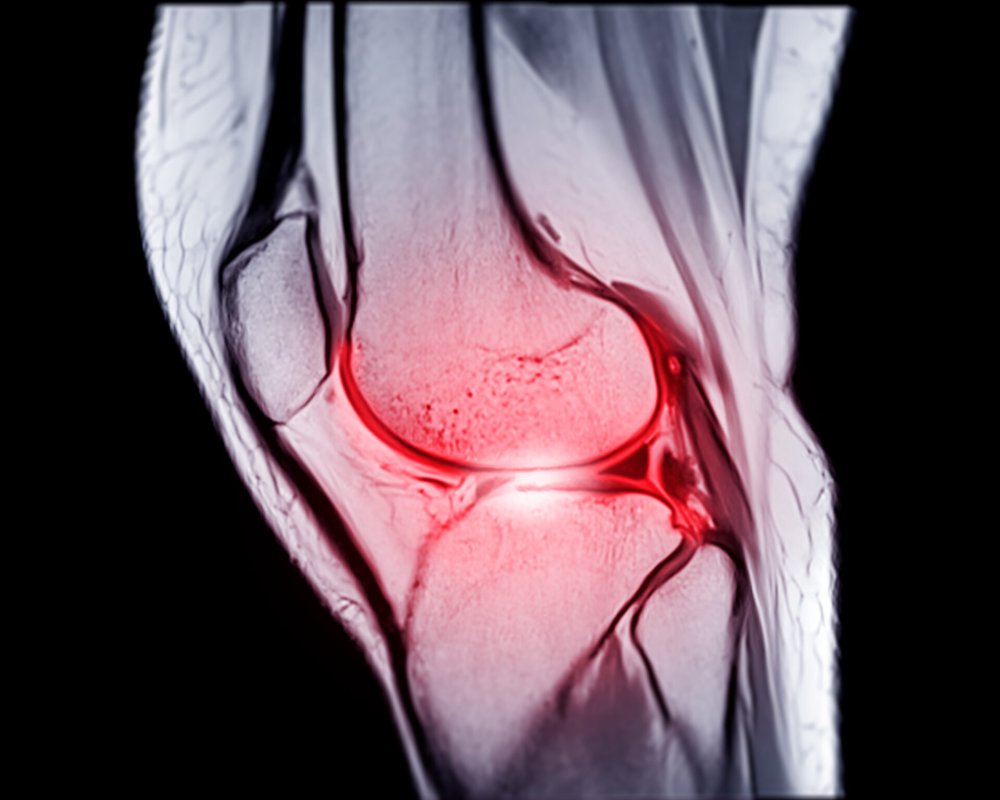

Diagnosing an ACL injury involves a physical examination, during which an orthopaedic surgeon will take your medical history, examine your knee for range of motion, stability, tenderness, and swelling, and may order X-rays to check for any fractures. In many cases, an MRI of the knee may also be prescribed to provide more information if the history and examination are inconclusive regarding an ACL tear.